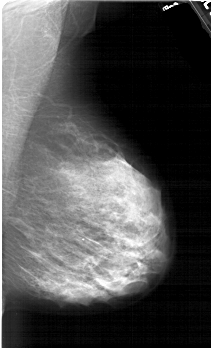

A_1983_1.LEFT_MLO

LEFT_MLO LINES 6421 PIXELS_PER_LINE 3886 BITS_PER_PIXEL 12 RESOLUTION 43.5 OVERLAY